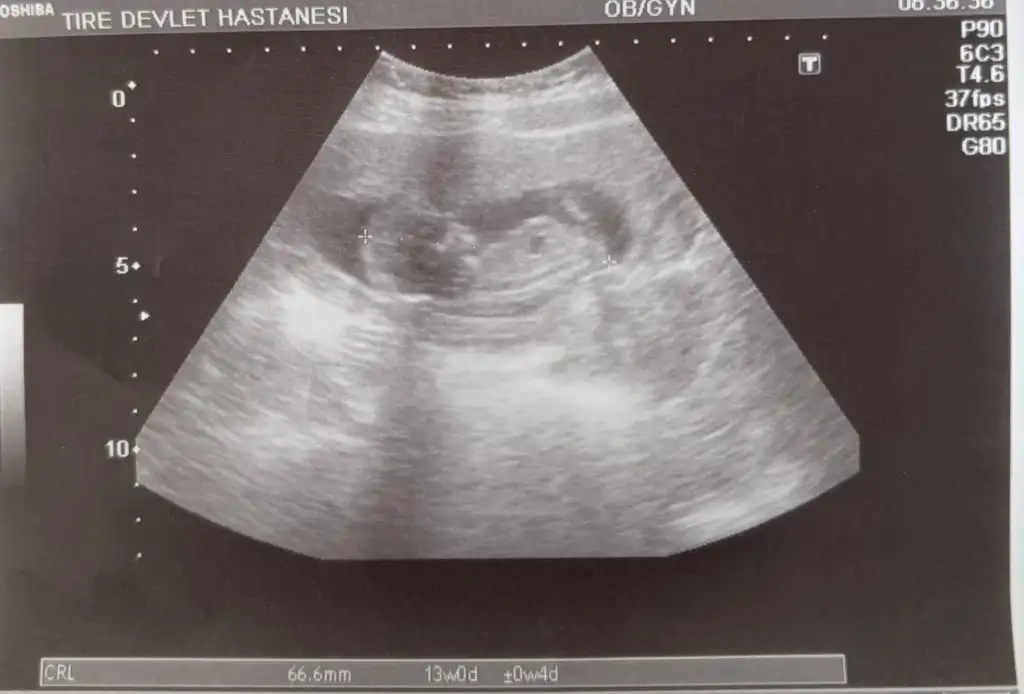

I ikizcan ❤️❤️ Kayıtlı Üye 11 Nisan 2021 712 639 53 33 22 Temmuz 2024 Konu Sahibi Konu Sahibi Melek3458 #84 avokadolupijama .!.: Erkek yada kız her türlü sağ salim sağlıkla kucağına almak nasip olsun Genişletmek için tıkla... Merhabalar kontrolden geldim tahmininizi öğrenebilir miyim Eklentiler IMG_5003.webp 21,1 KB · Görüntüleme: 53

avokadolupijama .!.: Erkek yada kız her türlü sağ salim sağlıkla kucağına almak nasip olsun Genişletmek için tıkla... Merhabalar kontrolden geldim tahmininizi öğrenebilir miyim